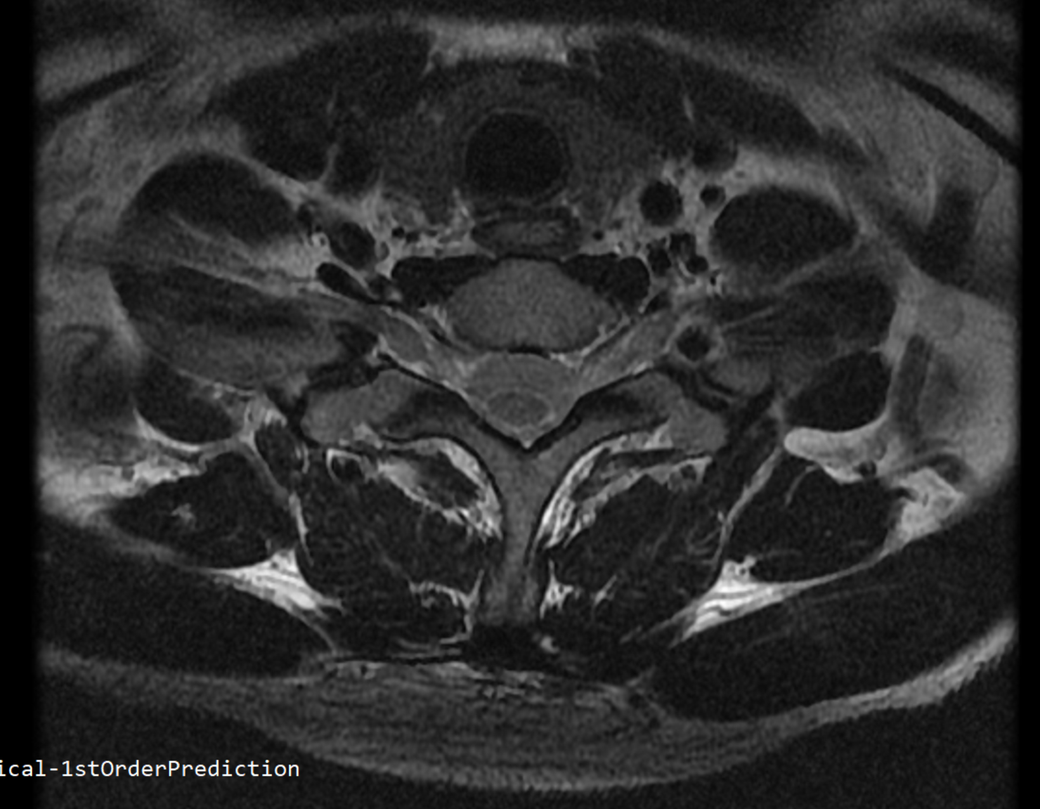

안녕하세요 목 경추 상단부터 순서대로 mri 촬영인데요

전체적으로 봐주시면 감사하겠습니다

하단8번 신경쪽도 나오는건지.. 봐주시면 감사하겠습니다

• 4번 째 사진